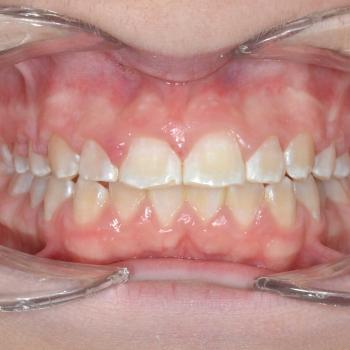

Gergő és édesanyja fogorvosi javaslatra keresett fel, a bal felső 2. kisőrlő hibás pozíciója miatt. A konzultáció során egyértelművé vált, hogy az előbb említett fog helyét teljes mértékben elfoglalták az előtte, illetve mögötte elhelyezkedő fogak, gyakorlatilag 0mm helyet hagyva a probléma megoldására. Ilyen esetekben felmerül a szájpadi irányba kiszorult fog eltávolítása, de a felső fogívben tapasztalható résesség a helyteremtés mellett szólt.

A kezelés első lépéseként Frog készülékkel hátrafelé mozdítottuk a bal felső első nagyőrlőt, ezzel elrendezve a nagyőrlők érintkezését, másfelől 4mm helyet teremtve a második kisőrlő számára. Ez a hely még nem volt elegendő, így rögzített fogszabályozóval zártuk a nagymetszők közötti, illetve az első kisőrlő előtti rést, mellyel további 2.5mm helyet nyertünk. Az így már 6.5mm-es rés elegendő volt ahhoz, hogy a kiszorult kisőrlőt bemozdítsuk a kívánt pozícióba, ezzel kialakítva egy funkcionálisan megfelelő és esztétikus felső fogívet. Mivel a harapás korrekciója, azaz a funkció helyreállítása kizárólag a felső fogív kezelésével is kivitelezhető volt, így a szülők nem kérték az alsó fogív torlódásának a megoldását.

A kezelés teljes időtartama: 2 év